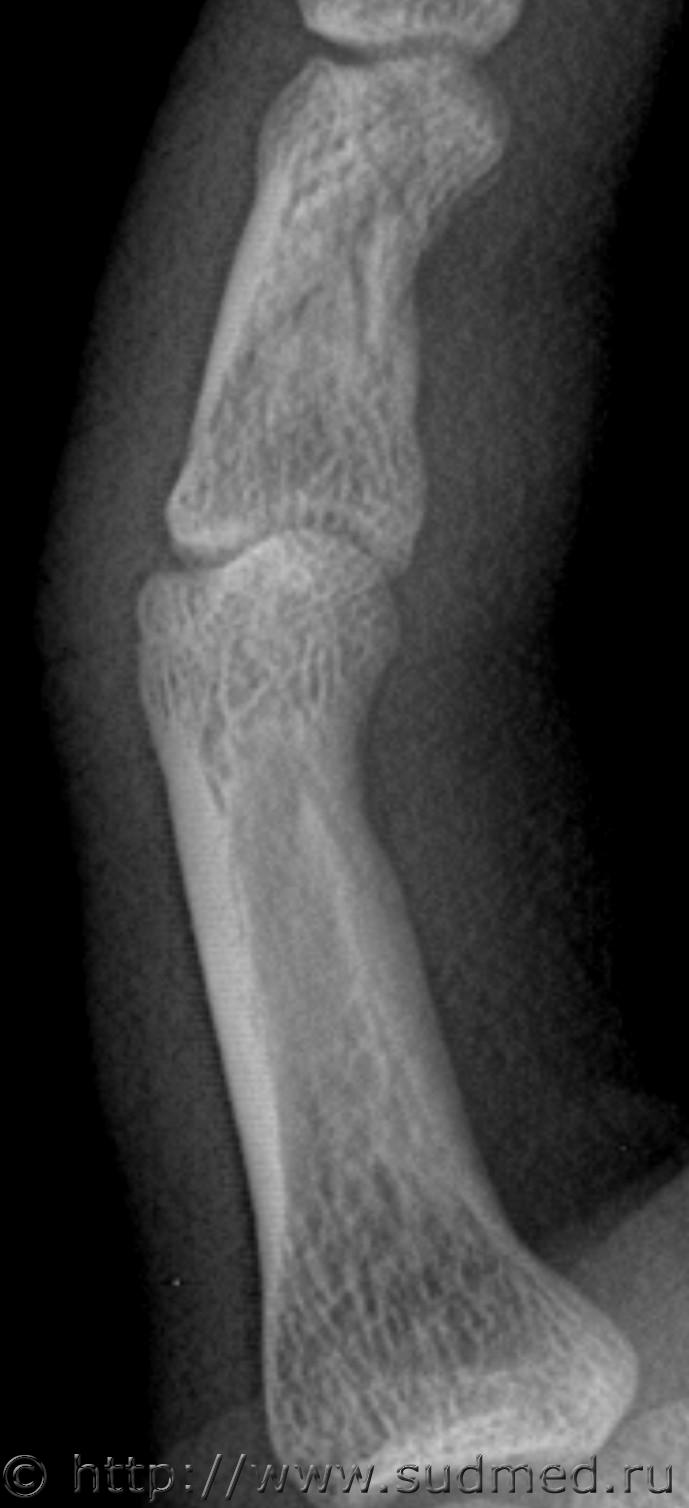

Следующий снимок сделал через 100 дней после травмы, по просьбе экспертов.

Второй снимок, 100 дней после травмы. На рентгеновской пленке.

Заключение: на представленной рентгенограмме 5 пальца левой кисти в 2-х проекциях от (100 после травмы) костно-травматических изменений не выявлено.

Снимок через 100 дней после травмы на рентгеновской пленке остался у экспертов, я его отсканировал перед тем как отдать:

Больше вопросов и предположений вызывает не основная, а средняя фаланга. Если бы она так выглядела через 100 дней после травмы, можно было бы согласиться, что несколько месяцев назад был перелом средней фаланги. Через 13 дней перелом так выглядеть не может. Вероятно, имеется какая-то индивидуальная особенность или когда-то давно (многие месяцы-годы назад) был перелом средней фаланги мизинца. Основная фаланга особых вопросов не вызывает: согласен с рентгенологами по поводу отсутствия достоверных рентгенологических признаков перелома.